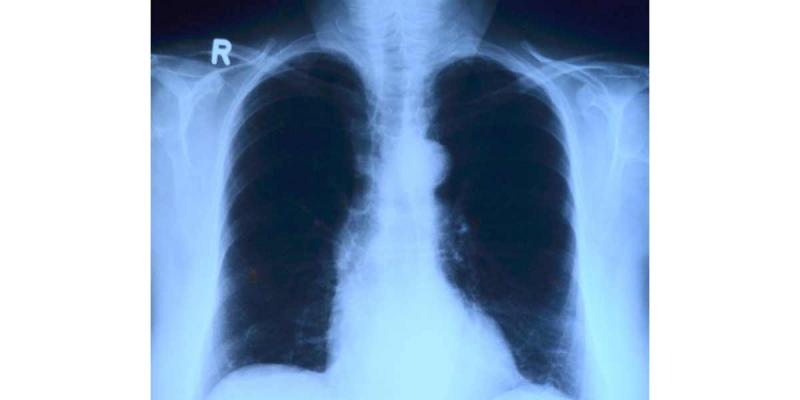

Radiografía de Torax

De momento, el proyecto es una aplicación informática, creada por estos estudiantes de ingeniería, y que está centrada en Inteligencia Artificial. El test se realiza en la web de forma muy sencilla, bastaría con introducir la radiografía de un paciente y, en unos segundos, la app señala con qué probabilidad ese paciente podría ser enfermo de COVID-19.

El modelo ha sido entrenado con cuatro categorías de radiografías, las correspondientes a pacientes con neumonía atribuida a coronavirus, con neumonías víricas y bacterianas y con ambos pulmones sanos; asimismo existe una cuarta categoría donde encajan las imágenes fallidas.

Los dos estudiantes de Ingeniería de la Universidad Europea garantizan que las casi 8.000 radiografías que han utilizado en el entrenamiento han sido verificadas, ya que proceden de la Universidad de Ottawa, del Centro Nacional de Radiología Intensivista de Italia, de las bases de datos que están utilizando los profesionales sanitarios durante la pandemia y de un médico español que ha compartido decenas de radiografías online.

Estos estudiantes de ingeniería aseguran que el modelo es muy prometedor, que tiene un "97,7% de acierto". El siguiente paso sería seguir entrenando el modelo con más radiografías y hacer un estudio clínico para poder probarlo.